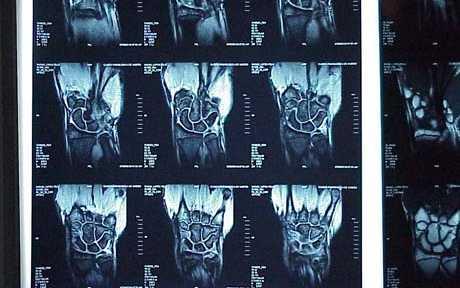

Slike u dijagnozi

Postavljanje dijagnoze samo na osnovi MR-a ili drugih dijagnostičkih tehnologija, naročito u ortopediji, nije moguće